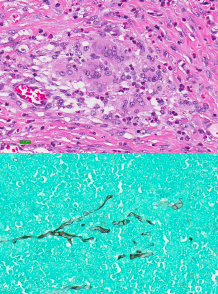

Chronic Pancreatitis

Et: idiopathic (#1), IBD, Cholangitis, Biliary obx, DM, Hepatic lipidosis, drugs

Sig: Older, cats

Cs: subclinical Cats

Dogs: chronic intermitting GI signs

can cause EPI and DM

Dt: Suspicion, low-grade inflammation

Lymphocytic-plasmacytic inflammation, fibrosis and

atrophy most common

US + PL will look normal